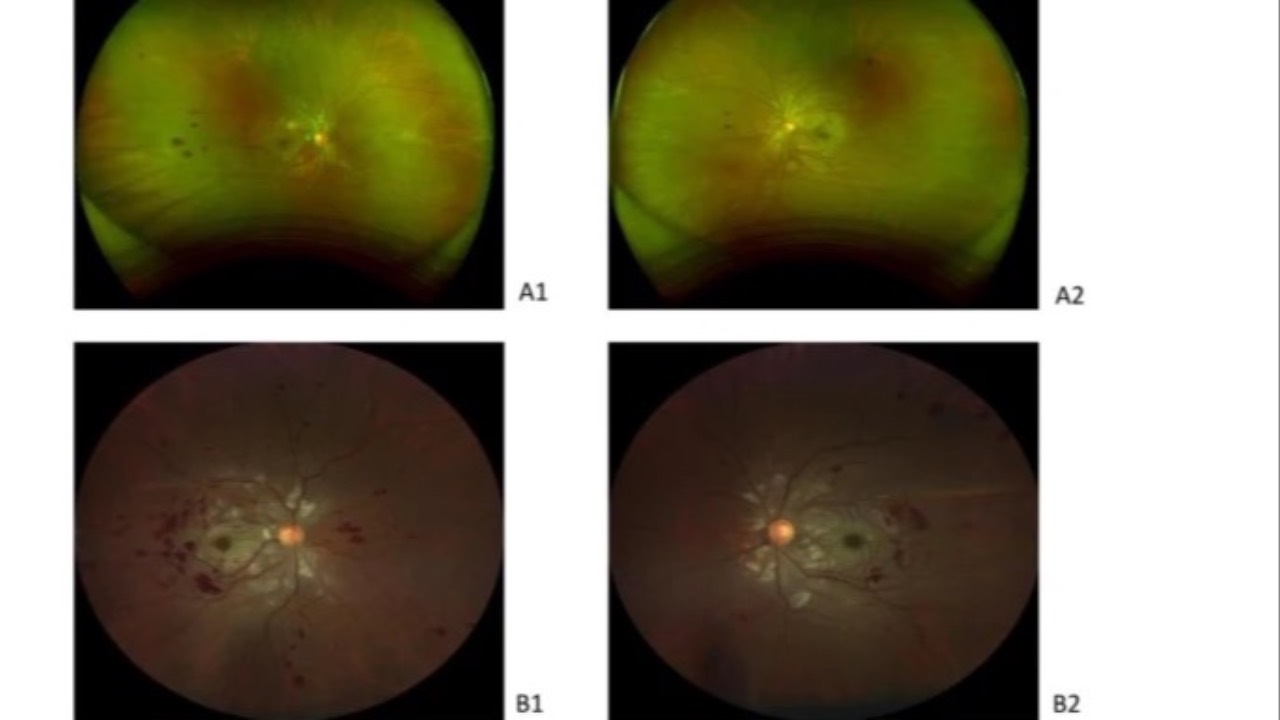

Purtscher-Like Retinopathy with Systemic Lupus Erythematosus

BMC Ophthalmology recently published a case of a 25-year-old patient who presented with sudden bilateral vision loss, revealing a rare case of simultaneous bilateral Purtscher-like retinopathy associated with systemic lupus erythematosus (SLE).

Exam showed retinal edema, artery narrowing, and s...